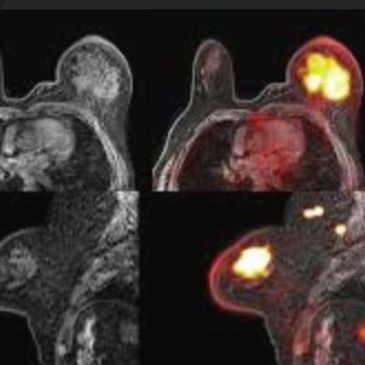

Principle: Combines metabolic information (PET) with superior soft-tissue contrast of MRI; simultaneous acquisition minimizes misregistration.

Advantages:

Limitations:

Performance:

Clinical Role: